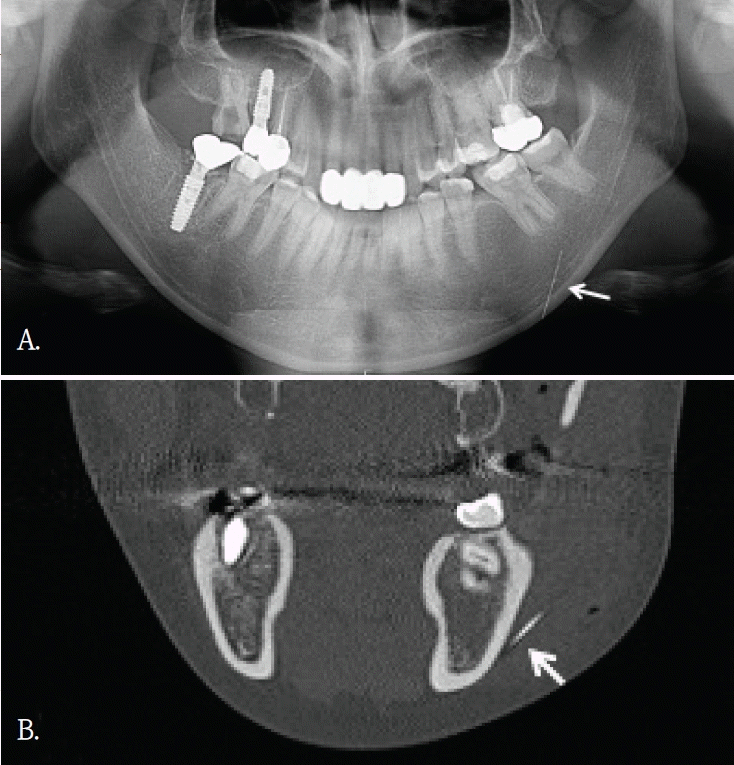

Fig. 3.

A. Panoramic radiograph shows a long, thin, linear radiopaque foreign body along the left mandibular body and inferior border (arrow). B. Coronal cone-beam computed tomographic image demonstrates that the linear radiopaque foreign body is located in the buccal soft tissue lateral to the mandible (arrow).

좌측 안면 부종으로 타원에서 의뢰된 30대 여자환자의 파노라마방사선영상에서 좌측 하악체 및 하연부를 따라 길이가 약 7cm로 측정된, 가는 선 모양의 방사선불투과성 이물질이 관찰되었다(Fig. 3A). 그러나 파노라마방사선영상에서 이물질의 협·설측 위치 및 하악골 내 포함여부를 명확히 판단하기 어려웠다. 이에 위치 및 주변 구조물과의 관계를 평가하기 위해 콘빔CT검사를 시행하였다. 콘빔CT에서 이물질은 좌측 하악체 외측 피질골 바깥의 협측 연조직에서 관찰되었다(Fig. 3B). 영상소견을 바탕으로 구강 내 접근을 통해 외과적 제거술이 시행 되었고 제거된 이물질은 부러진 주사바늘로 확인되었다.- 증례 4

콘빔CT는 해부학적 구조물이나 이물질 위치를 확인하고, 인접 구조물과의 관계를 파악하는데 유리하다. 2차원 영상에서 발생되는 중첩을 줄이고, 3차원적인 위치정보를 제공함으로써 치과 임플란트 치료계획이나 치아 교정 진단과정에서 필수적인 영상검사이다. 또한, 임플란트 식립이나 매복치 발거등 외과적 치료과정에서도 진입 경로 결정에 도움을 주어 술 후 합병증을 감소시킨다.콘빔CT의 원래 촬영 목적과는 관계없이, 우연히 발견되는 소견들이 있다. 이러한 소견의 빈도는 24.6~94.3%로 보고마다 매우 다양하다[1,2]. 소아 및 청소년연령군에서의 빈도도 0.4~80.3%로 다양하지만 매우 자주 발견된다[3]. 발견되는 부위는 치아 및 치조골을 벗어난 부위가 대부분으로 주로 부비동 및 비강, 혈관, 연조직, 경추이다[1-3]. 그러므로, 콘빔CT 검사할 때 촬영목적 부위 뿐 만 아니라 그 외 다른 부위의 판독도 충분히 이루어져야 한다[2,4,8]. 특히 어린 환자에서는 방사선방어를 고려하여, 관심부위 뿐 만 아니라 콘빔CT영상에 포함된 모든 부위에서 영상판독이 충분히 이루어져야 한다[3]. 우연히 발견되는 소견의 양상도 매우 다양하다. 부비동 및 비강에서는 점막비후, 점액저류낭, 비중격만곡이 많이 발견되고, 혈관부위에서는 경동맥석회화가 주로 발견된다. 연조직에서는 편도석, 경동설골인대골화가 주로 발견되는 소견이다[1-3]. 대부분 해부학적 변이이거나 의학적 조치가 필요하지 않은 경우이다.하지만 추적검사나 치료가 필요한 임상적으로 의미가 있는 소견들도 매우 다양한 빈도로 발견된다. 최소 0.4%에서 최대 37%까지로 전체의 약 1/6-1/3 정도에서 발견되어 주의깊은 콘빔CT 영상판독이 필요하다. 이들 소견중에는 치근단병소, 치성낭, 종양도 있었으며[1-3], 오랜 기간 동안 인지하지 못했던 이물질도 발견된다[1,4,6,8].우연히 발견된 이물질들은 치조골 및 악골 부위가 아닌 다른 부위에서 많이 관찰되었다. 교정목적으로 촬영된 콘빔CT에서 비강내에 플라스틱 이물질이 우연히 발견되어 이비인후과 의뢰 후 이물질을 제거한 증례보고가 있다[4]. 증상이 없어서 이물질의 유무를 알 수 없었지만, 콘빔CT에서 비강내 이물질이 확인되어 외과적으로 제거한 증례보고도 있다[5,6]. 증상이 있어 촬영한 상악 견치 치근단방사선사진에서 모호한 방사선불투과성 이물질이 관찰되어, 이후 촬영한 콘빔CT에서 이물질이 유리조각으로 확인된 증례보고도 있다[8]. 이 증례는 유리같은 이물질은 치근단이나 파노라마방사선사진에서는 명확하게 관찰되지 않았기에 콘빔CT검사가 매우 유용하였던 경우이다.증례 1에서도 초진시 파노라마영상에서는 유리조각을 관찰할 수 없었기에 연조직 병변으로 진단되었으나, 재내원후 촬영된 콘빔CT영상에서 연조직내에 있었던 이물질임으로 확인된 경우이다. 윗입술에 있었던 유리조각이 방사선불투과성 물질이였지만, 상악 전치부와 중첩되어 파노라마방사선영상에서 뚜렷하게 구분되지 않았다.증례 5와 같이 파노라마방사선영상에서 모호하게 관찰되었거나 증례 3과 4같이 파노라마방사선영상에서 협-설위치를 명확하게 알 수 없었던 경우, 콘빔CT영상에서 임상적으로 의미있는 이물질임을 확인되었고 외과적 치료가 시행되었던 증례들이다. 특히, 이들 소견은 악골이 아닌 안면 연조직 부위에서 관찰되어, 주의 깊은 영상판독의 중요성을 다시금 일깨워 준다.한편, 안면미용시술을 받은 환자들이 치과에 많이 내원하면서 우연히 발견되는 이물질 소견 중 하나가 미용 필러이다[9]. 치과의사들에게 아직은 익숙하지 않은 방사선영상 소견이고 부위도 치아나 악골이 아닌 연조직부위에서 관찰되기에 영상 판독에서 배제될 가능성이 있다. 미용필러도 파노라마방사선 영상에서보다는 콘빔CT영상에서 위치나 형태, 양상을 잘 관찰할 수 있다.본 증례들은 파노라마방사선영상에서 인지되지 않았던 이물질 3증례와 파노라마방사선영상에서 의심된 이물질이 콘빔 CT에서 위치와 형태가 명확히 규명된 2증례를 포함한다. 이를 통해 악안면 콘빔CT 판독 시 촬영 목적 부위에 국한하지 않고 영상에 포함된 전체 영역을 체계적으로 검토함으로써, 이물질과 같은 우연히 발견되는 소견이 누락되는 것을 줄일 수 있음을 알았다. 또한 추가 촬영이나 불필요한 검사로 인한 방사선 노출을 예방하여, 콘빔CT 검사의 정당성과 임상적 유효성을 강화하는 뒷받침이 됨을 알았다.